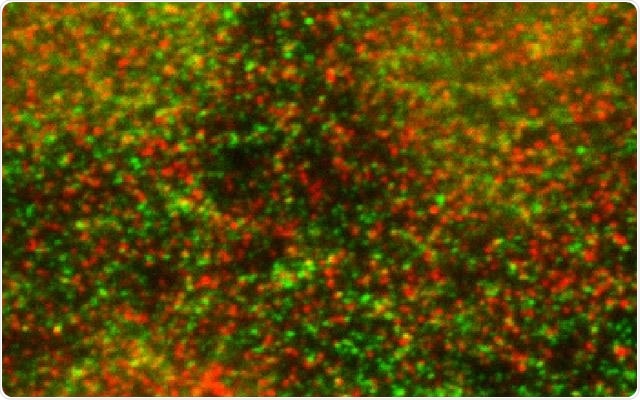

Endothelial cells stained with antibodies to track the GPCR (shown in green) and E3 ligase (shown in red) and detected by immunofluorescence confocal microscopy. Credit UC San Diego Health

For the study, Trejo and colleagues studied endothelial cells and how the function of GPCRs is affected by ubiquitination (the tagging of proteins with ubiquitin). This ubiquitination instructs the cell’s waste disposal system to degrade that protein.